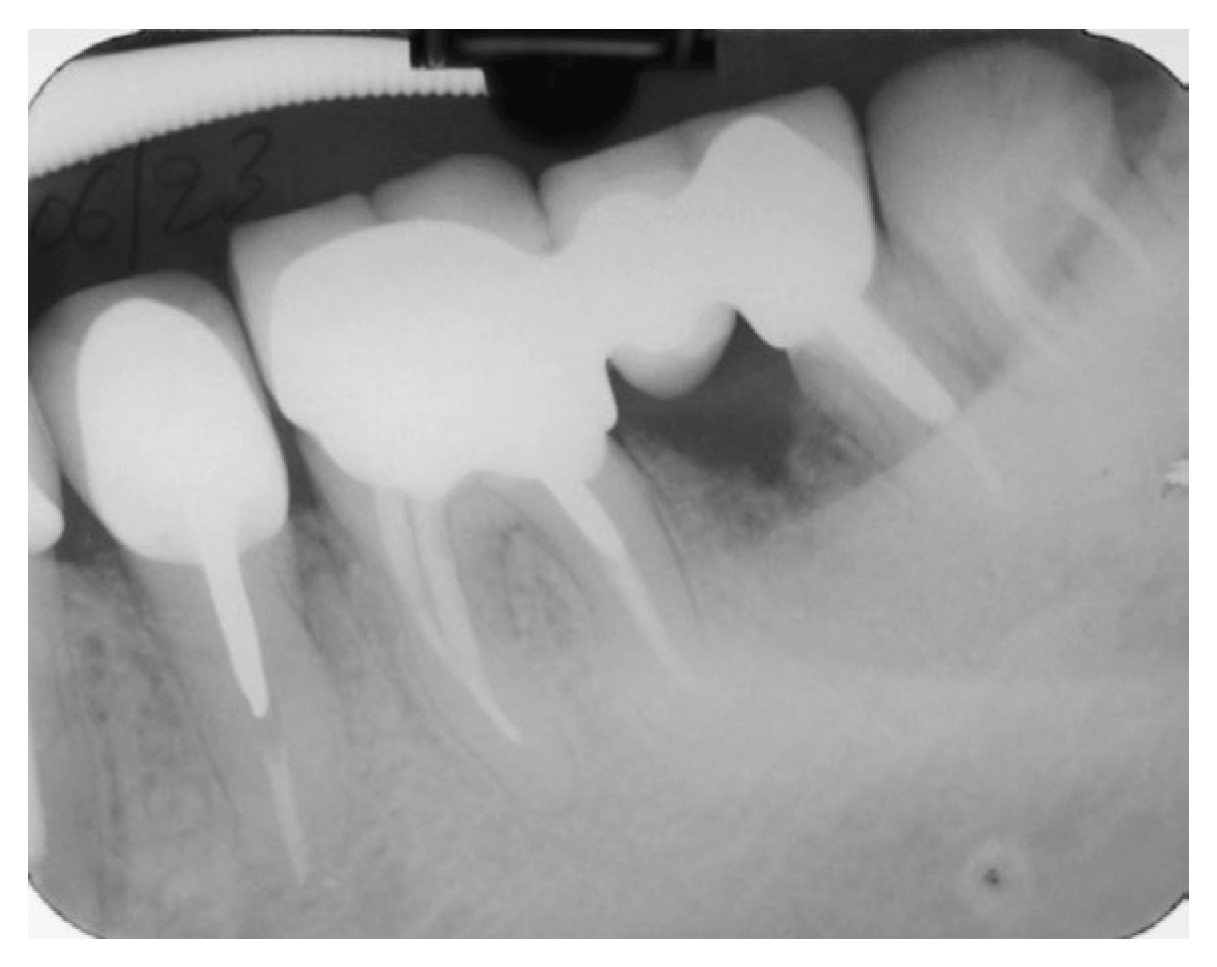

A periapical radiograph in the molar region of #46-47 teeth revealed that there was a radiolucent area in the middle third of the mesial root of tooth #47. This lesion was located mesially and it seems to be rather well defined in this area but coronally the bone loss had a J-shape appearance. In addition, subgingival carries in the distal roots of #47 and #46 were also detected (Figure 2). Both teeth had been restored with cast posts and splinted fused to metal ceramic crowns. Crestal bone between the two teeth appeared to be moderately resorbed.

Figure 2. Periapical X-Ray of #46, #47.